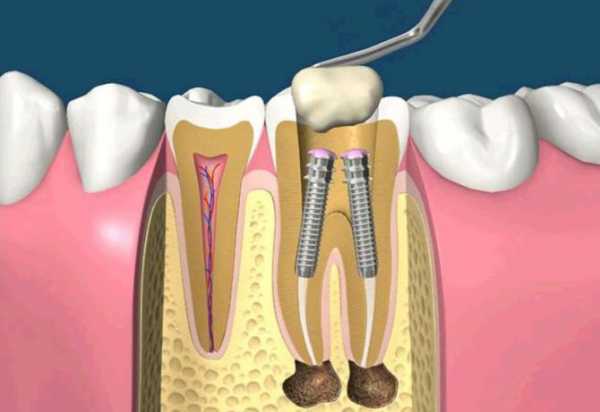

Для восстановления и исправления зубов сегодня разработаны десятки методов, каждый из которых призван быстро и безболезненно решать определенную клиническую задачу. При кариозных разрушениях лучше всего себя зарекомендовали вкладки, а при отсутствии у зуба опоры на помощь приходят штифты. Установка штифта при зубном протезировании осуществляется следующим образом: один конец стержня вкручивают в корневой канал, на другом крепят новый красивый зуб.

Штифтом стоматологи называют особый стержень с резьбой. С ее помощью один конец штифта вкручивается в корень зуба, на второй конец конструкции устанавливается протез. Штифтовый метод наращивания зубов актуален в тех случаях, когда верхняя часть зуба сильно разрушена, а корневые каналы в нормальном состоянии.

Установленный штифт